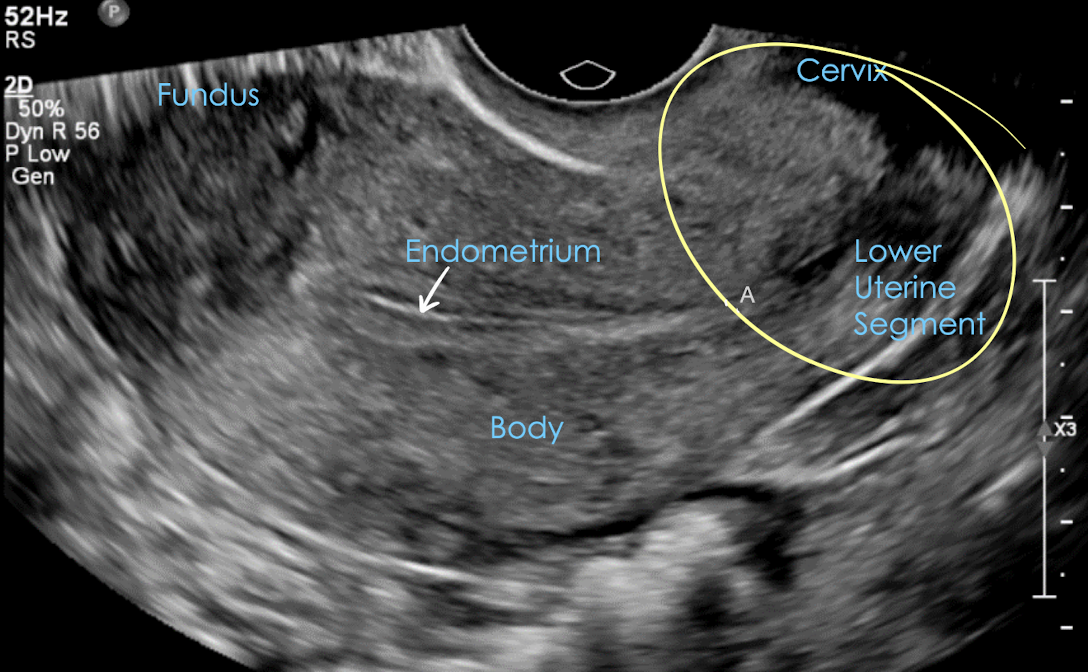

transvaginal pelvic anatomy in LONG

** patient must empty bladder